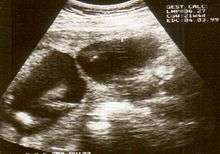

Amniotic band syndrome is often difficult to detect before birth as the individual strands are small and hard to see on ultrasound. Often the bands are detected indirectly because of the constrictions and swelling upon limbs, digits, etc. Misdiagnosis is also common, so if there are any signs of amniotic bands, further detailed ultrasound tests should be done to assess the severity. 3D ultrasound and MRI can be used for more detailed and accurate diagnosis of bands and the resulting damage/danger to the fetus.